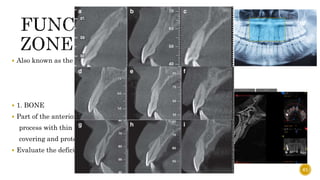

 According to Tolstunov, a Diplomate of the American Board of Oral

Implantology/Implant Dentistry, the alveolar jaw can be divided into four regions or

“functional implant zones” with each region possessing "unique characteristics.

ZONE 1

 Also known as the “traumatic zone”

 1. BONE

 Part of the anterior maxilla is a protruding alveolar

process with thin labial and thick palatal cortical plates

covering and protecting upper front teeth.

 Evaluate the deficiency